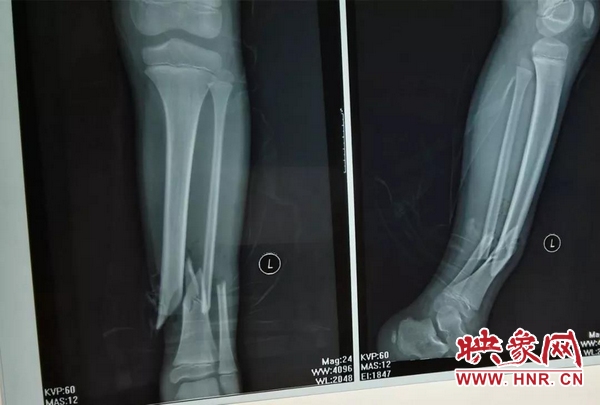

入院后,骨二科接诊的郑医生为小李完善各项检查,经X光片显示,小李是左侧胫腓骨粉碎性骨折(开放性),需要入院接受手术治疗。但是,患者及其母亲王女士对将要进行手术显得十分恐惧,担心手术会给小李的腿部留下巨大且难看的瘢痕。

当天晚上,小李接受了手术治疗,手术由张世清主任主刀,郑富文医生担任辅助。在C型臂透视下,骨二科团队为患者实施了切开复位双排组合式外固定架固定术,手术过程顺利,骨折对位线良好,术中出血5ml,仅用几个小孔就完成了外固定且位置满意。